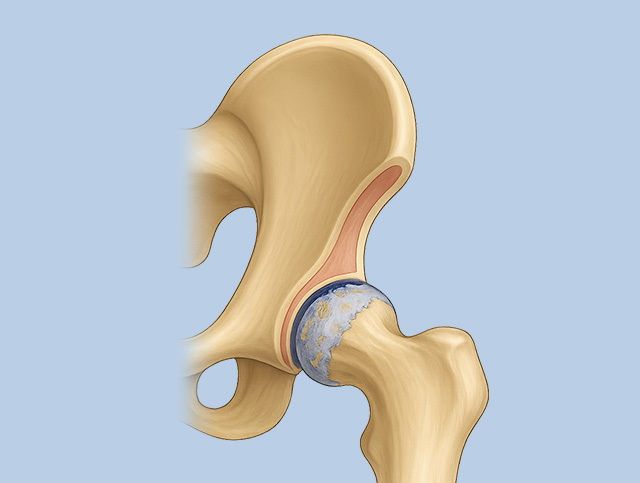

고관절 충돌증후군

허벅지뼈의 둥근 머리와 골반의 움푹 들어간 고관절 연결 부위가 부딪히면서 염증, 통증 발생

골반 앞쪽이나 사타구니 쪽 통증, 다리를 돌리거나 양반다리 하기 어려워짐. 악화되면 허벅지, 엉덩이, 허리까지 통증 확산

퇴행성 고관절염

고관절에 염증이 발생하여 통증, 절뚝거림, 고관절 움직임 제약

고관절 연골 두께 감소, 활액막 두꺼워짐, 물이 차는 증상 등 발생